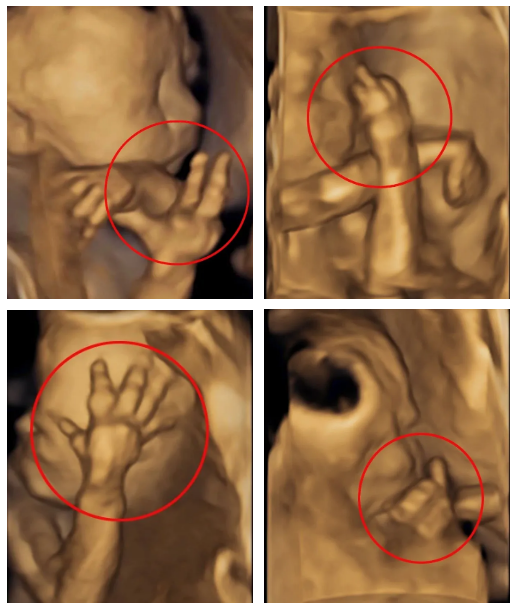

瞧瞧下图,有位宝妈做产检的时候,发现胎儿竟然在肚子里像拍照那样比了个“耶”~还有各种手势,简直玩嗨了。

看了这神奇的图片,很多人也不免好奇,到底是啥检查,看得这么清晰呢?

宝妈做的检查其实是超声影像(四维彩超),这是孕中期特别重要的一项B超检查。主要目的是检查胎儿结构畸形,预防出生缺陷。